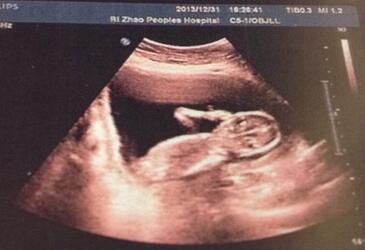

怀孕14周胎儿彩超图?怀孕14周的胎儿有多大呢?身高、体重分别是多少?胎儿在母体里面能够做哪些动作?这些都是孕妈妈关心的事情。下面,我们来看看怀孕14周胎儿彩超图,看看胎儿发育状态。

怀孕14周胎儿发育

1、目前胎儿有76-100毫米,体重大约28克,胎儿的手指已经开始长出指纹印,皮肤上覆盖了一层细细绒毛,头发也开始迅速的生长。

2、胎儿此时在妈妈的肚子里已经可以做很多事情了,如皱眉,做鬼脸,斜着眼睛,可能他也在吸吮自己的手指等,科学证明这些动作可以促进大脑的成长。